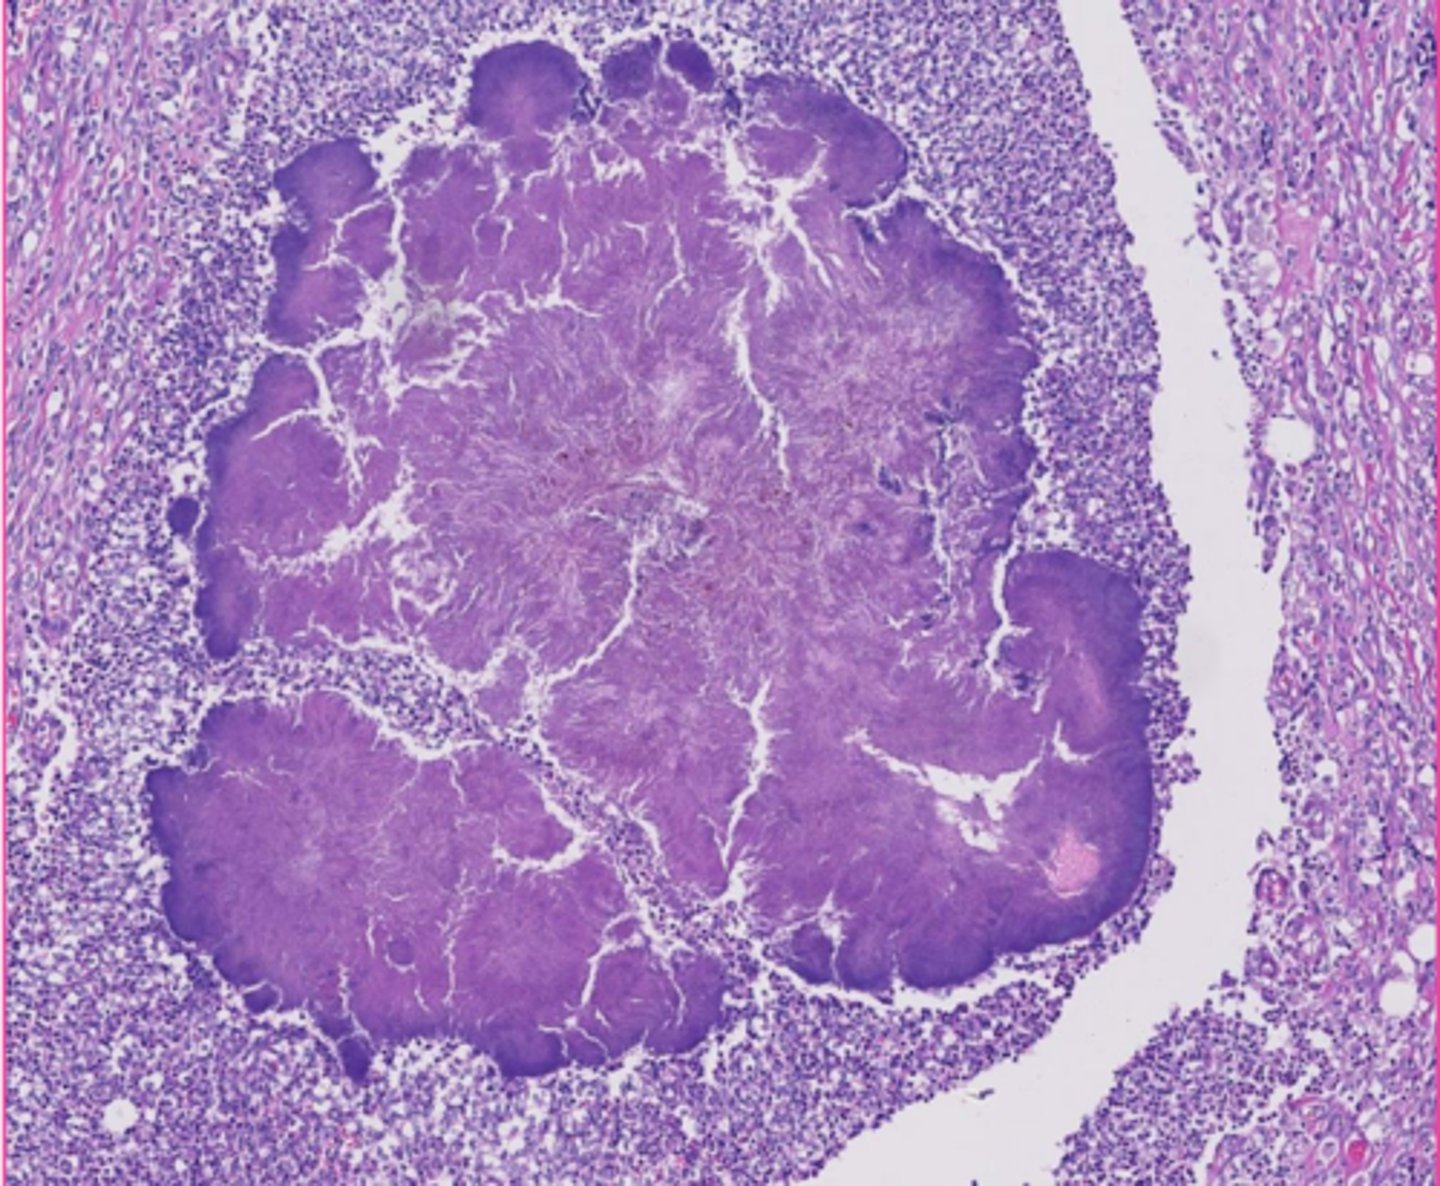

amyloid

describe the extracellular inclusion

<p>describe the extracellular inclusion</p>